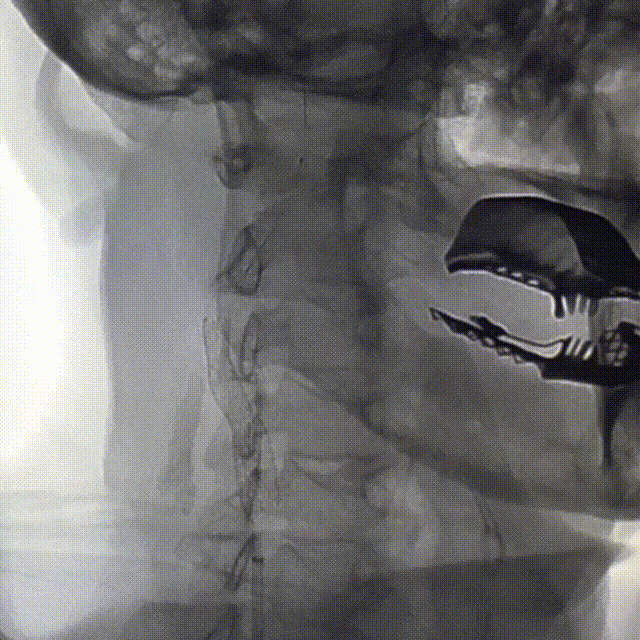

右颈内造影

动脉长鞘怎么置入桡路大腔,超薄无伤 | EasyMax™ Pro长鞘经桡入路辅助行颈内动脉支架植入术_https://www.jmylbn.com_新闻资讯_第2张

动脉长鞘怎么置入桡路大腔,超薄无伤 | EasyMax™ Pro长鞘经桡入路辅助行颈内动脉支架植入术_https://www.jmylbn.com_新闻资讯_第3张

DSA提示:右侧颈内动脉起始部重度狭窄(狭窄率约70%)。